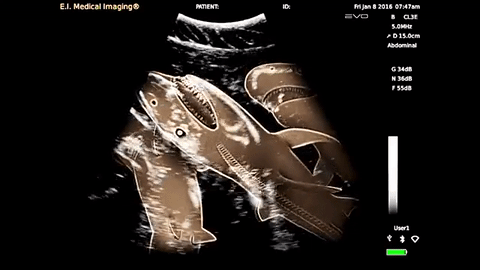

Check Out The First-Ever Shark Sonogram

It's jam-packed with little biting teeth! Aww!

Shark sonogram

Taken with a 12.5 foot pregnant tiger shark named "Emily," this novel event was performed to study the shark life cycle. The shark is carrying 20 pups, and in the past, researchers would have had to cut the shark open. Find out more about the shark pups and their mama here. Discovery

Scientists have captured the first-ever shark sonogram, and gosh is it cute. Or creepy. Mostly creepy.

A 12.5-foot tiger shark, named “Emily” by these humans but probably named something a lot cooler by her shark fam, carries 20 pups. Before this, sharks were killed and cut open to study pregnancies.

This aquatic gynecologist appointment will help scientists track where sharks go to give birth: If they go to a nursery field, that area could be preserved and protected from human activities.